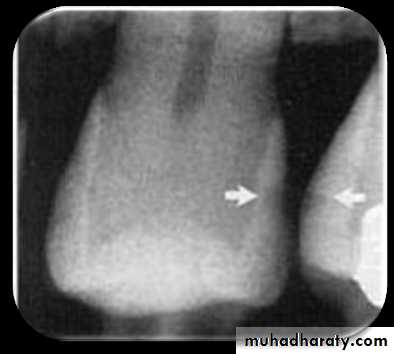

Root Surface Caries

Clinically root surface caries is easily detected on exposed root surface.The most common locations include the exposed root of the mandibular premolar and molar areas.

Radiographically the root surface caries appears as a cupped–out or crater shaped radiolucency just below the cemento-enamel junction.